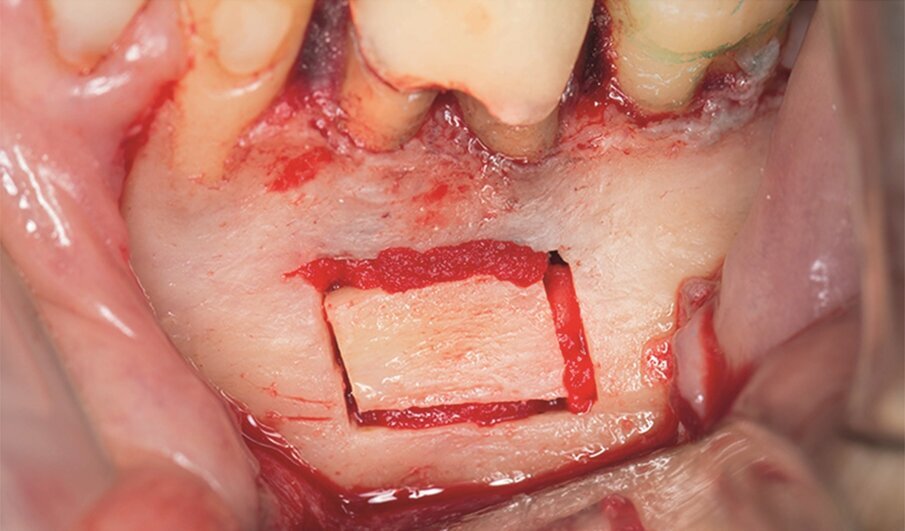

Fig. 1e–i: During microsurgery, the template was adjusted (e), …

… the limits of the cortical window were marked in the bone (f) …

… with a saw mounted in a Piezotome CUBE LED handpiece, then the bone was cut and removed (g & h) …

… to access the apical area and perform the apicectomy, apical cavity preparation and retro-filling of the mesial and distal roots (i).

Under local anaesthesia, a full thickness mucoperiosteal flap was reflected and the printed template was used to mark the cortical window, which was cut with a Piezotome CUBE LED handpiece (ACTEON), removed (Figs. 1e–h) and then placed in sterile saline. An apicectomy was done (Fig. 1i), and the mesial canals were retro-prepared with ultrasonic tips (NSK) and filled with EndoSequence BC RRM Fast Set Putty (Brasseler). The cortical window was then placed back and stabilized with collagen sponges in the gaps (collagen tape, Zimmer Biomet; Figs. 1j & k), and the ‑ap was sutured using 6/0 prolene suture material (Corpaul).